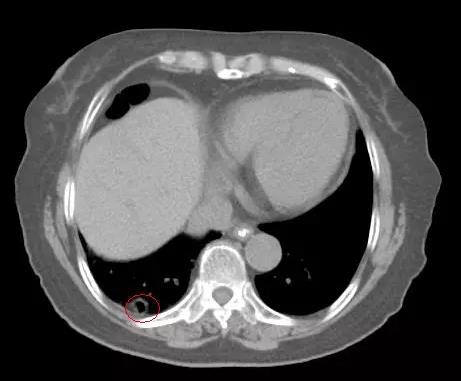

▲ 上图为曾被误诊为炎症的薄壁空洞,下图为增厚的空洞病灶,经穿刺后确诊为肺鳞癌的原发病灶